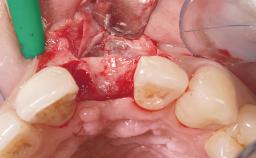

Immediate Flapless Placement of an Implant in a Maxillary Left Central Incisor Site

Pedro Tortamano, Luiz Otávio Alves Camargo

A 42-year-old female patient was referred to our clinic at the School of Dentistry of the University of São Paulo in November 2004, presenting a deficient restoration in the upper left central incisor. The clinical examination revealed no gingival retraction or any signs of gingival inflammation and, therefore, previous periodontal treatment was not considered. The patient presented a high lip line at full smile and a thin tissue biotype. This combination characterized a high-risk situation from an anatomic point of view, which required careful preoperative planning and cautious surgical execution.